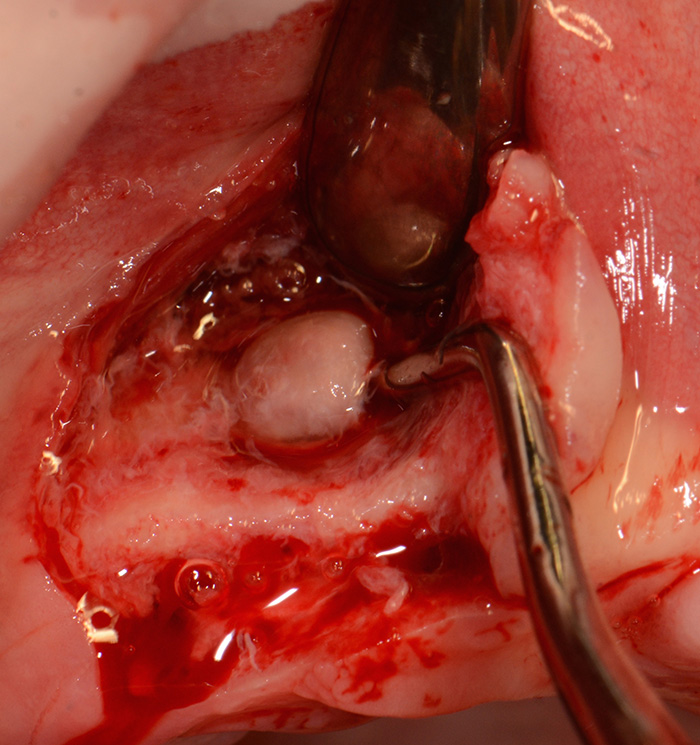

Fig. 5 : Décharge vestibulaire en distal de la cavité kystique et décollement d’un lambeau de pleine épaisseur.

Énucléation du kyste et parage de la cavité kystique.